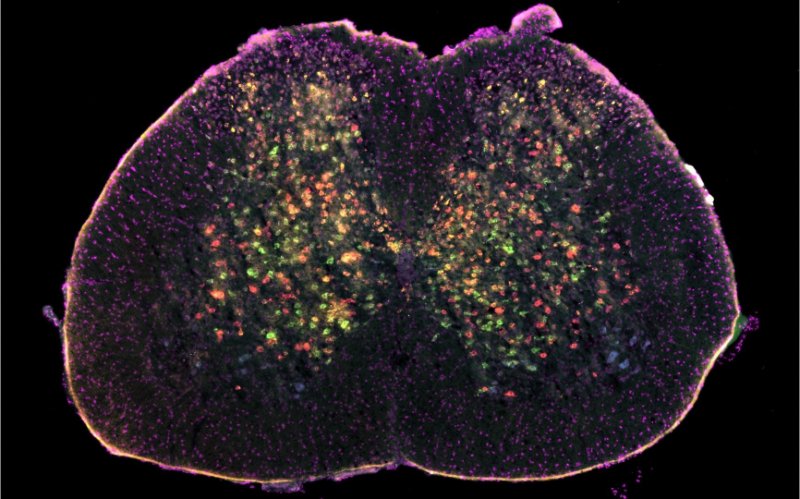

Researchers use AI to uncover the progression of ALS

By using AI, researchers looked at specific cells in the spinal cord that are affected early on by ALS, before the motor neurons start to die.